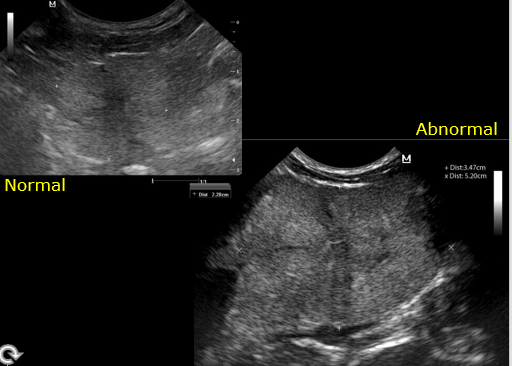

What is the normal appearance of prostate ultrasound?

What is this appearance?

Immature Hypoechoic

Discuss the appearance here

Mature – hard to make out margin

Smooth and rounded

Under 2cm

How does the overall echogenicity compare to the normal prostate?

What is the liekly differential?

Heterogenous

More echogenic

Bigger too

Diagnosis:

BPH

Cant rule out infection = not many cysts